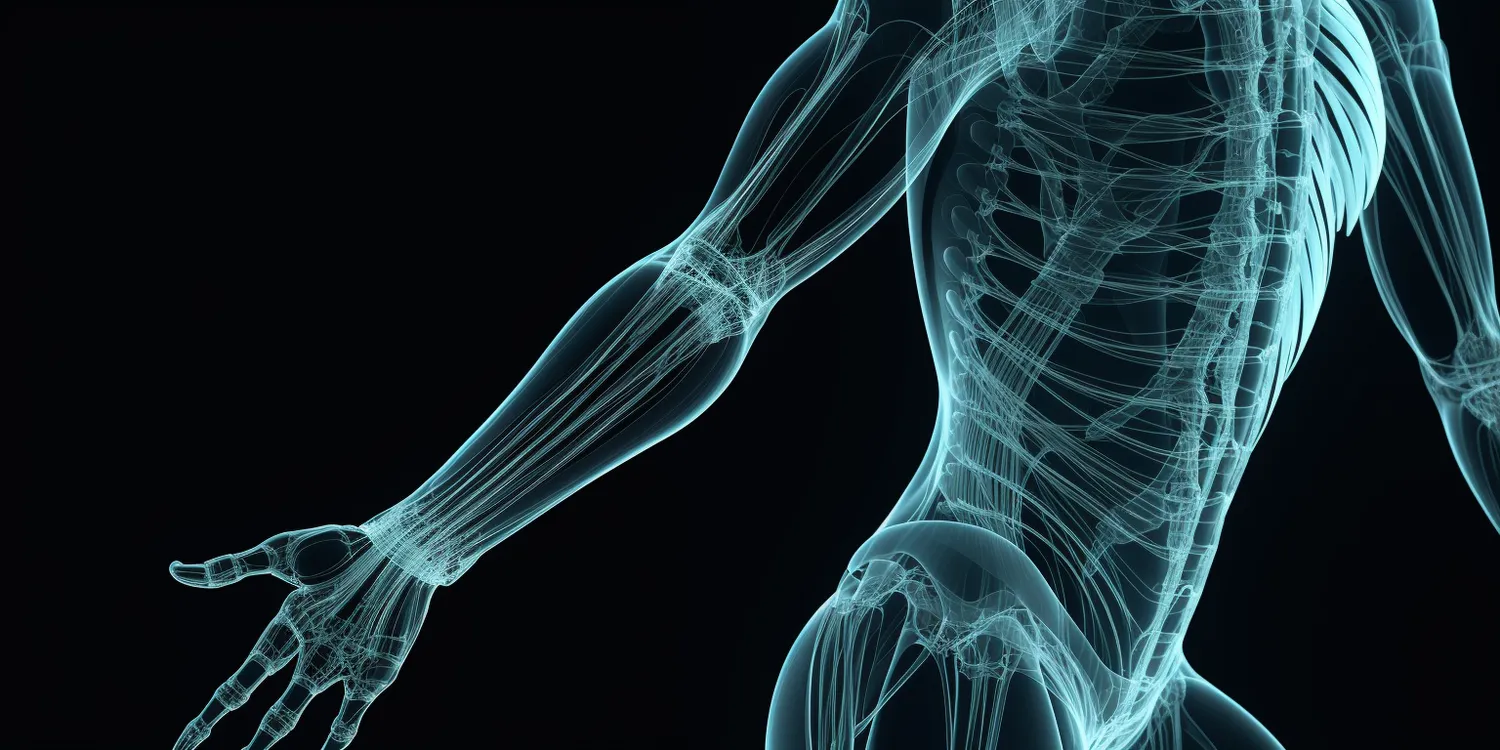

W rehabilitacji ogólnoustrojowej wykorzystuje się szereg metod, które mają na celu poprawę funkcjonowania organizmu pacjenta. Do najpopularniejszych z nich należy fizjoterapia, która obejmuje różnorodne techniki takie jak masaż, elektroterapia czy ultradźwięki. Te metody pomagają w redukcji bólu oraz poprawie krążenia krwi, co przyspiesza proces gojenia tkanek. Inną istotną metodą jest kinezyterapia, czyli terapia ruchem, która polega na wykonywaniu specjalnie dobranych ćwiczeń fizycznych. Ćwiczenia te mają na celu wzmocnienie mięśni, poprawę koordynacji oraz elastyczności ciała. W kontekście rehabilitacji ogólnoustrojowej nie można zapominać o psychoterapii, która wspiera pacjentów w radzeniu sobie z emocjami związanymi z chorobą lub urazem.

Rehabilitacja ogólnoustrojowa jest niezbędna w przypadku wielu schorzeń, które wpływają na sprawność fizyczną i jakość życia pacjentów. Do najczęstszych problemów zdrowotnych, które wymagają takiej formy terapii, należą schorzenia ortopedyczne, takie jak urazy stawów, złamania czy choroby zwyrodnieniowe. Osoby po operacjach ortopedycznych, takich jak artroskopia kolana czy wszczepienie endoprotezy, często potrzebują intensywnej rehabilitacji, aby przywrócić pełną funkcjonalność kończyn. Inną grupą pacjentów są osoby z chorobami neurologicznymi, takimi jak udar mózgu czy stwardnienie rozsiane, które mogą wymagać specjalistycznej rehabilitacji w celu poprawy koordynacji ruchowej oraz siły mięśniowej. Ponadto, rehabilitacja ogólnoustrojowa jest również istotna dla osób z przewlekłymi chorobami układu oddechowego, takimi jak astma czy przewlekła obturacyjna choroba płuc (POChP), które mogą korzystać z technik oddechowych oraz ćwiczeń poprawiających wydolność organizmu.